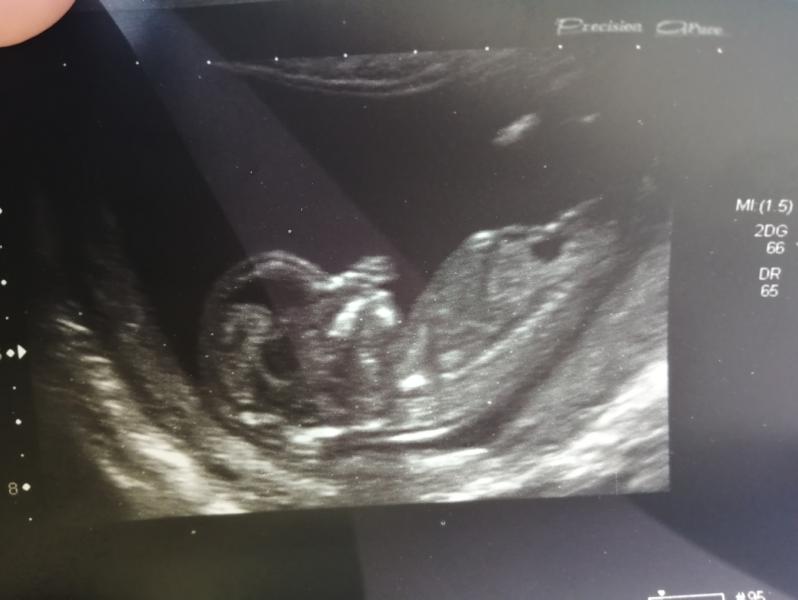

Пару дней назад был первый скрининг,

и у меня назрел вопрос, кто умеет определять пол по УЗИ? Давайте попробуем. Срок 13.2 недели. Я думаю, что девочка) 👩👧 #первыйпост #первыйскрининг #мальчикилидевочка

Мальчик?